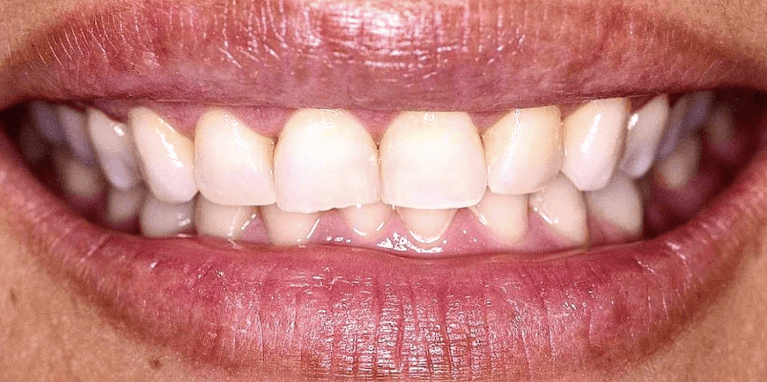

Invisalign Orthodontic treatment completed in 8 months to straighten teeth and improve esthetics.